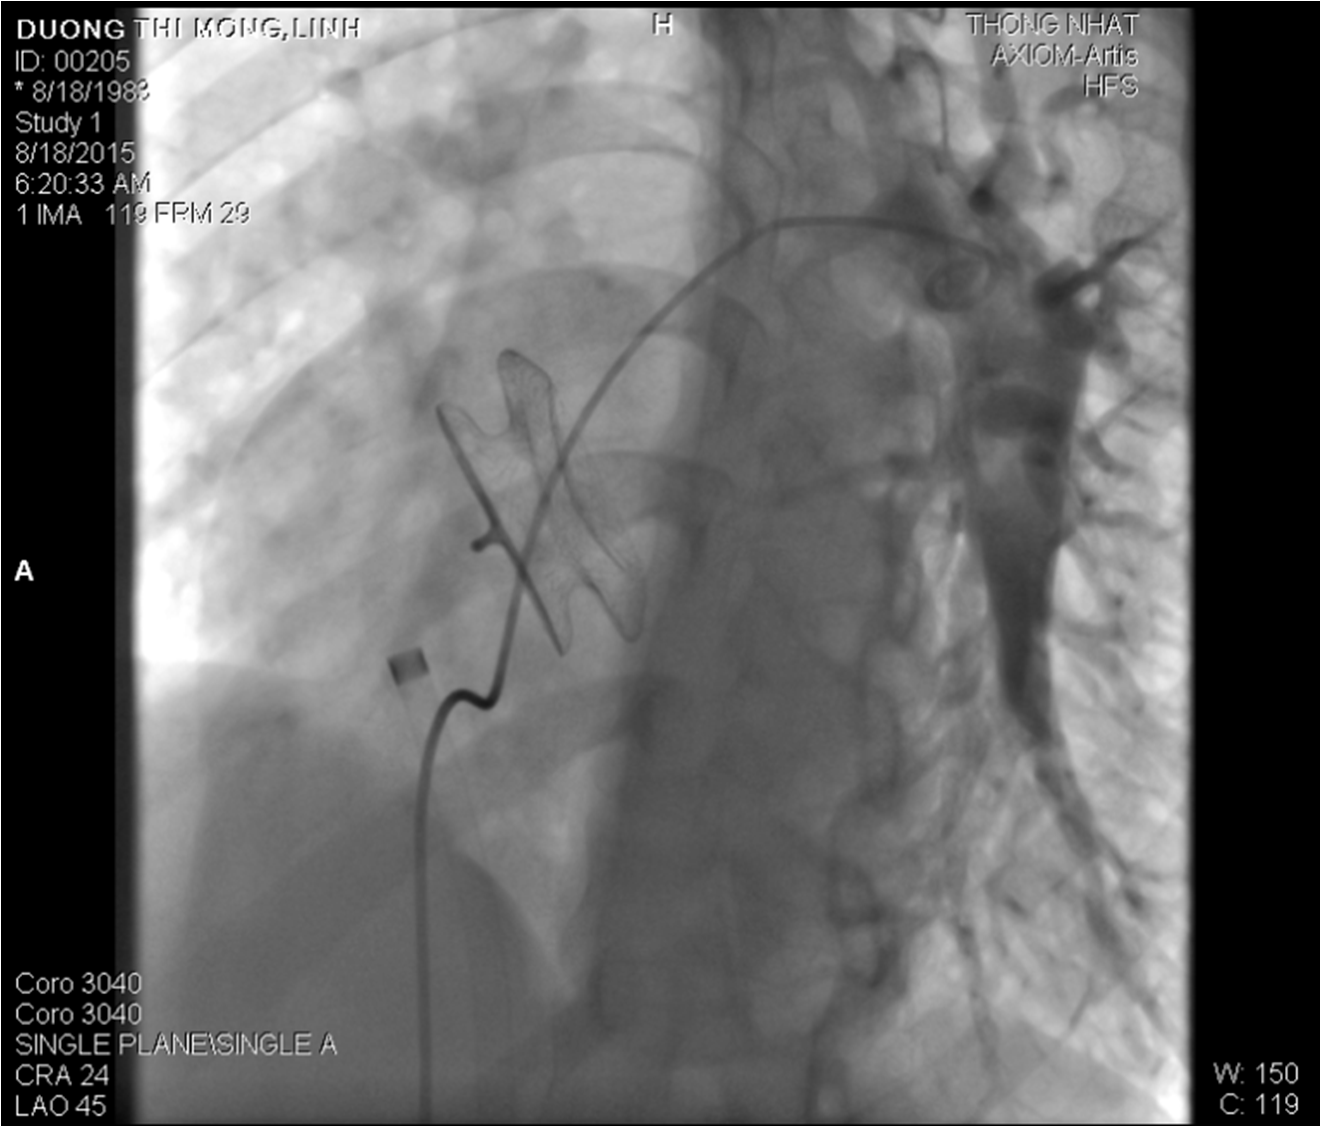

5.3 Can thiệp bệnh tim bẩm sinh:

Bít các lỗ thông bằng dù chuyên dụng trong và cận tim như Còn ống động mạch, Thông liên nhĩ, Thông liên thất… giúp phòng ngừa suy tim do luồng máu thông bất thường

Một trường hợp bít Thông liên nhĩ lỗ lớn bằng dù Amplazer